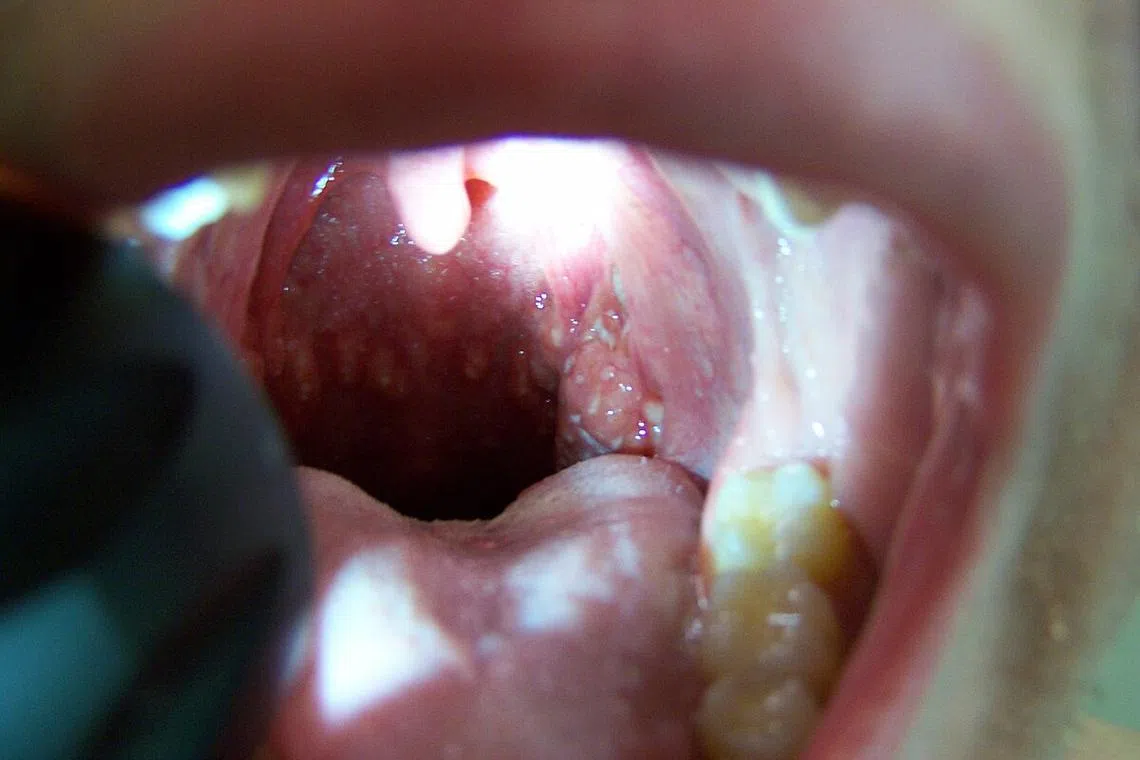

Herpangina is an infectious condition where one develops blisters and ulcers in the mouth.

PHOTO ILLUSTRATION: WIKIMEDIA COMMONS

It was then that I finally realised what I had caught – my son’s herpangina, which is an infectious condition where one develops blisters and ulcers in the mouth.

Herpangina is closely related to the better-known hand, foot and mouth disease (HFMD), as both conditions are caused by the same group of viruses belonging to the Coxsackie and enterovirus family.

The infection usually involves the back of the soft palate, causing a sore throat and pain on swallowing food or fluids, and is often accompanied by a high fever.